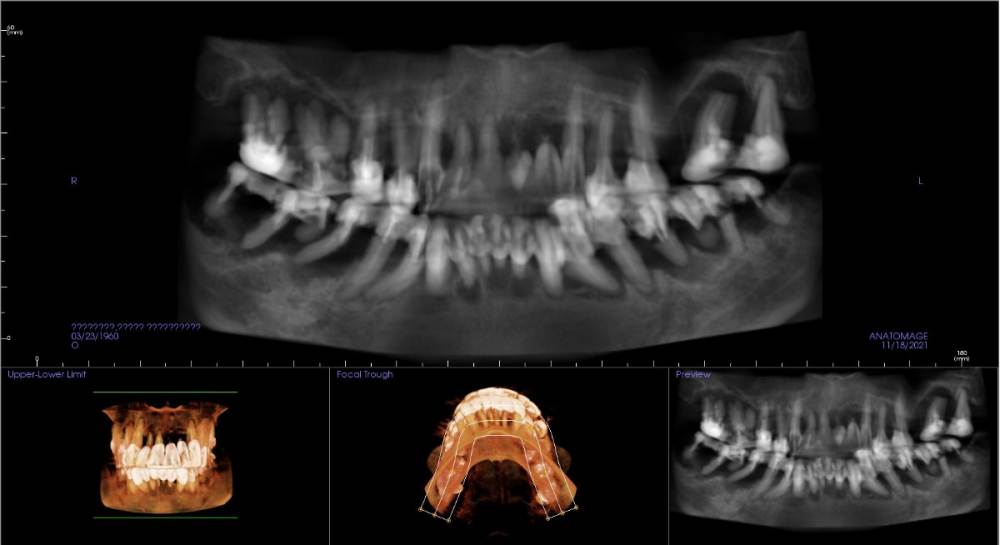

Irouil Опубликовано 20 ноября, 2021 Поделиться Опубликовано 20 ноября, 2021 Уважаемые коллеги! В клинику обратилась пациентка, 60 г.р., хочет зубы. Провела консультацию у меня (хирург) и у ортопеда. Я прилагаю скрин с орто реконструкции ее КТ, генерализованный пародонтит, все шатается и пахнет. Для меня очевидный план лечения - тотальное удаление, редукция гребней и ол-он-фо два раза. Минимальная редукция на верхней челюсти - примерно 9 мм от нынешнего зенита 1.1 зуба (который, на секундочку, в 14 мм от резцового края). и вот тут возникает недопонимание. Ортопед считает, что сделать хорошую эстетику в таком варианте не выйдет, поэтому настаивает на съемном протезировании с балкой. Чего я не догоняю? Ортопед от прямого ответа уходит. Фото во рту нет, извините. 1 Ссылка на комментарий

pit Опубликовано 23 ноября, 2021 Поделиться Опубликовано 23 ноября, 2021 (изменено) 20.11.2021 в 17:09, Irouil сказал: Уважаемые коллеги! В клинику обратилась пациентка, 60 г.р., хочет зубы. Провела консультацию у меня (хирург) и у ортопеда. Я прилагаю скрин с орто реконструкции ее КТ, генерализованный пародонтит, все шатается и пахнет. Для меня очевидный план лечения - тотальное удаление, редукция гребней и ол-он-фо два раза. Минимальная редукция на верхней челюсти - примерно 9 мм от нынешнего зенита 1.1 зуба (который, на секундочку, в 14 мм от резцового края). и вот тут возникает недопонимание. Ортопед считает, что сделать хорошую эстетику в таком варианте не выйдет, поэтому настаивает на съемном протезировании с балкой. Чего я не догоняю? Ортопед от прямого ответа уходит. Фото во рту нет, извините. Вы уж простите меня, но с ортопедом оба не догоняете)))). Так как стартовая информация по кейсу не предоставлена. 1. Ортопедический аспект: нет фото профиля нижней трети лица. 2. Хирургический аспект: при АО4 на в/ч явно будет установка транссинус и возможно, назолифтинг, для этого нужен КТ срез до среднего носового хода минимум. По существу заданных вопросов: В данном кейсе по в/ч 2 принципиальных решения- несъмная конструкция FP-3 (по Мишу) и ПСП с опорой на импланты или без. Опасения ортопеда вполне обоснованы, так как ключевым аспектом является поддержка мягких тканей. Сделав несъемный протез с уменьшением размера дуги верхней челюсти уменьшится поддержка мягких тканей, что приведет к уплощению верхней губы и большей выраженностью носогубных складок. Иными словами Вы, визуально, состарите паца на 5-7 лет. При увеличении дуги в/ч можно получить выраженный балкон на протезе, который гигиенически и эстетически (при улыбке некрасивая горизонтальная складка в области фильтрума) будет не выгоден. Учитывая, что при исходной ситуации нет никакой возможности выполнить адекватную примерку не удаляя зубов, я бы провел пациента двухэтапно, через удаления и временный ПСП. Спустя 2 месяца сделал бы примерку на приточке и получил бы 100% ясность. Позиционирование имплантов: 5-1(2)-1(2)-5 вполне приемлема. Как для АО4, так и для балки с уровня МЮ. Выполнив такое позиционирование Вы не промахнетесь с обоими планами, так как оно будет универсально для съемного и несъемного протезов. Но здесь Вам необходим транссинусальный доступ и, при редукции гребня, возможно, назолифтинг. Но если идти таким путем, необходимо тщательно просчитать оба плана и все обговорить с пациентом. Если Вы сделаете несъемные времянки, а лицо пациенту не понравится, то спокойно перейти на съемный протез Изменено 23 ноября, 2021 пользователем pit 4 1 2 Ссылка на комментарий